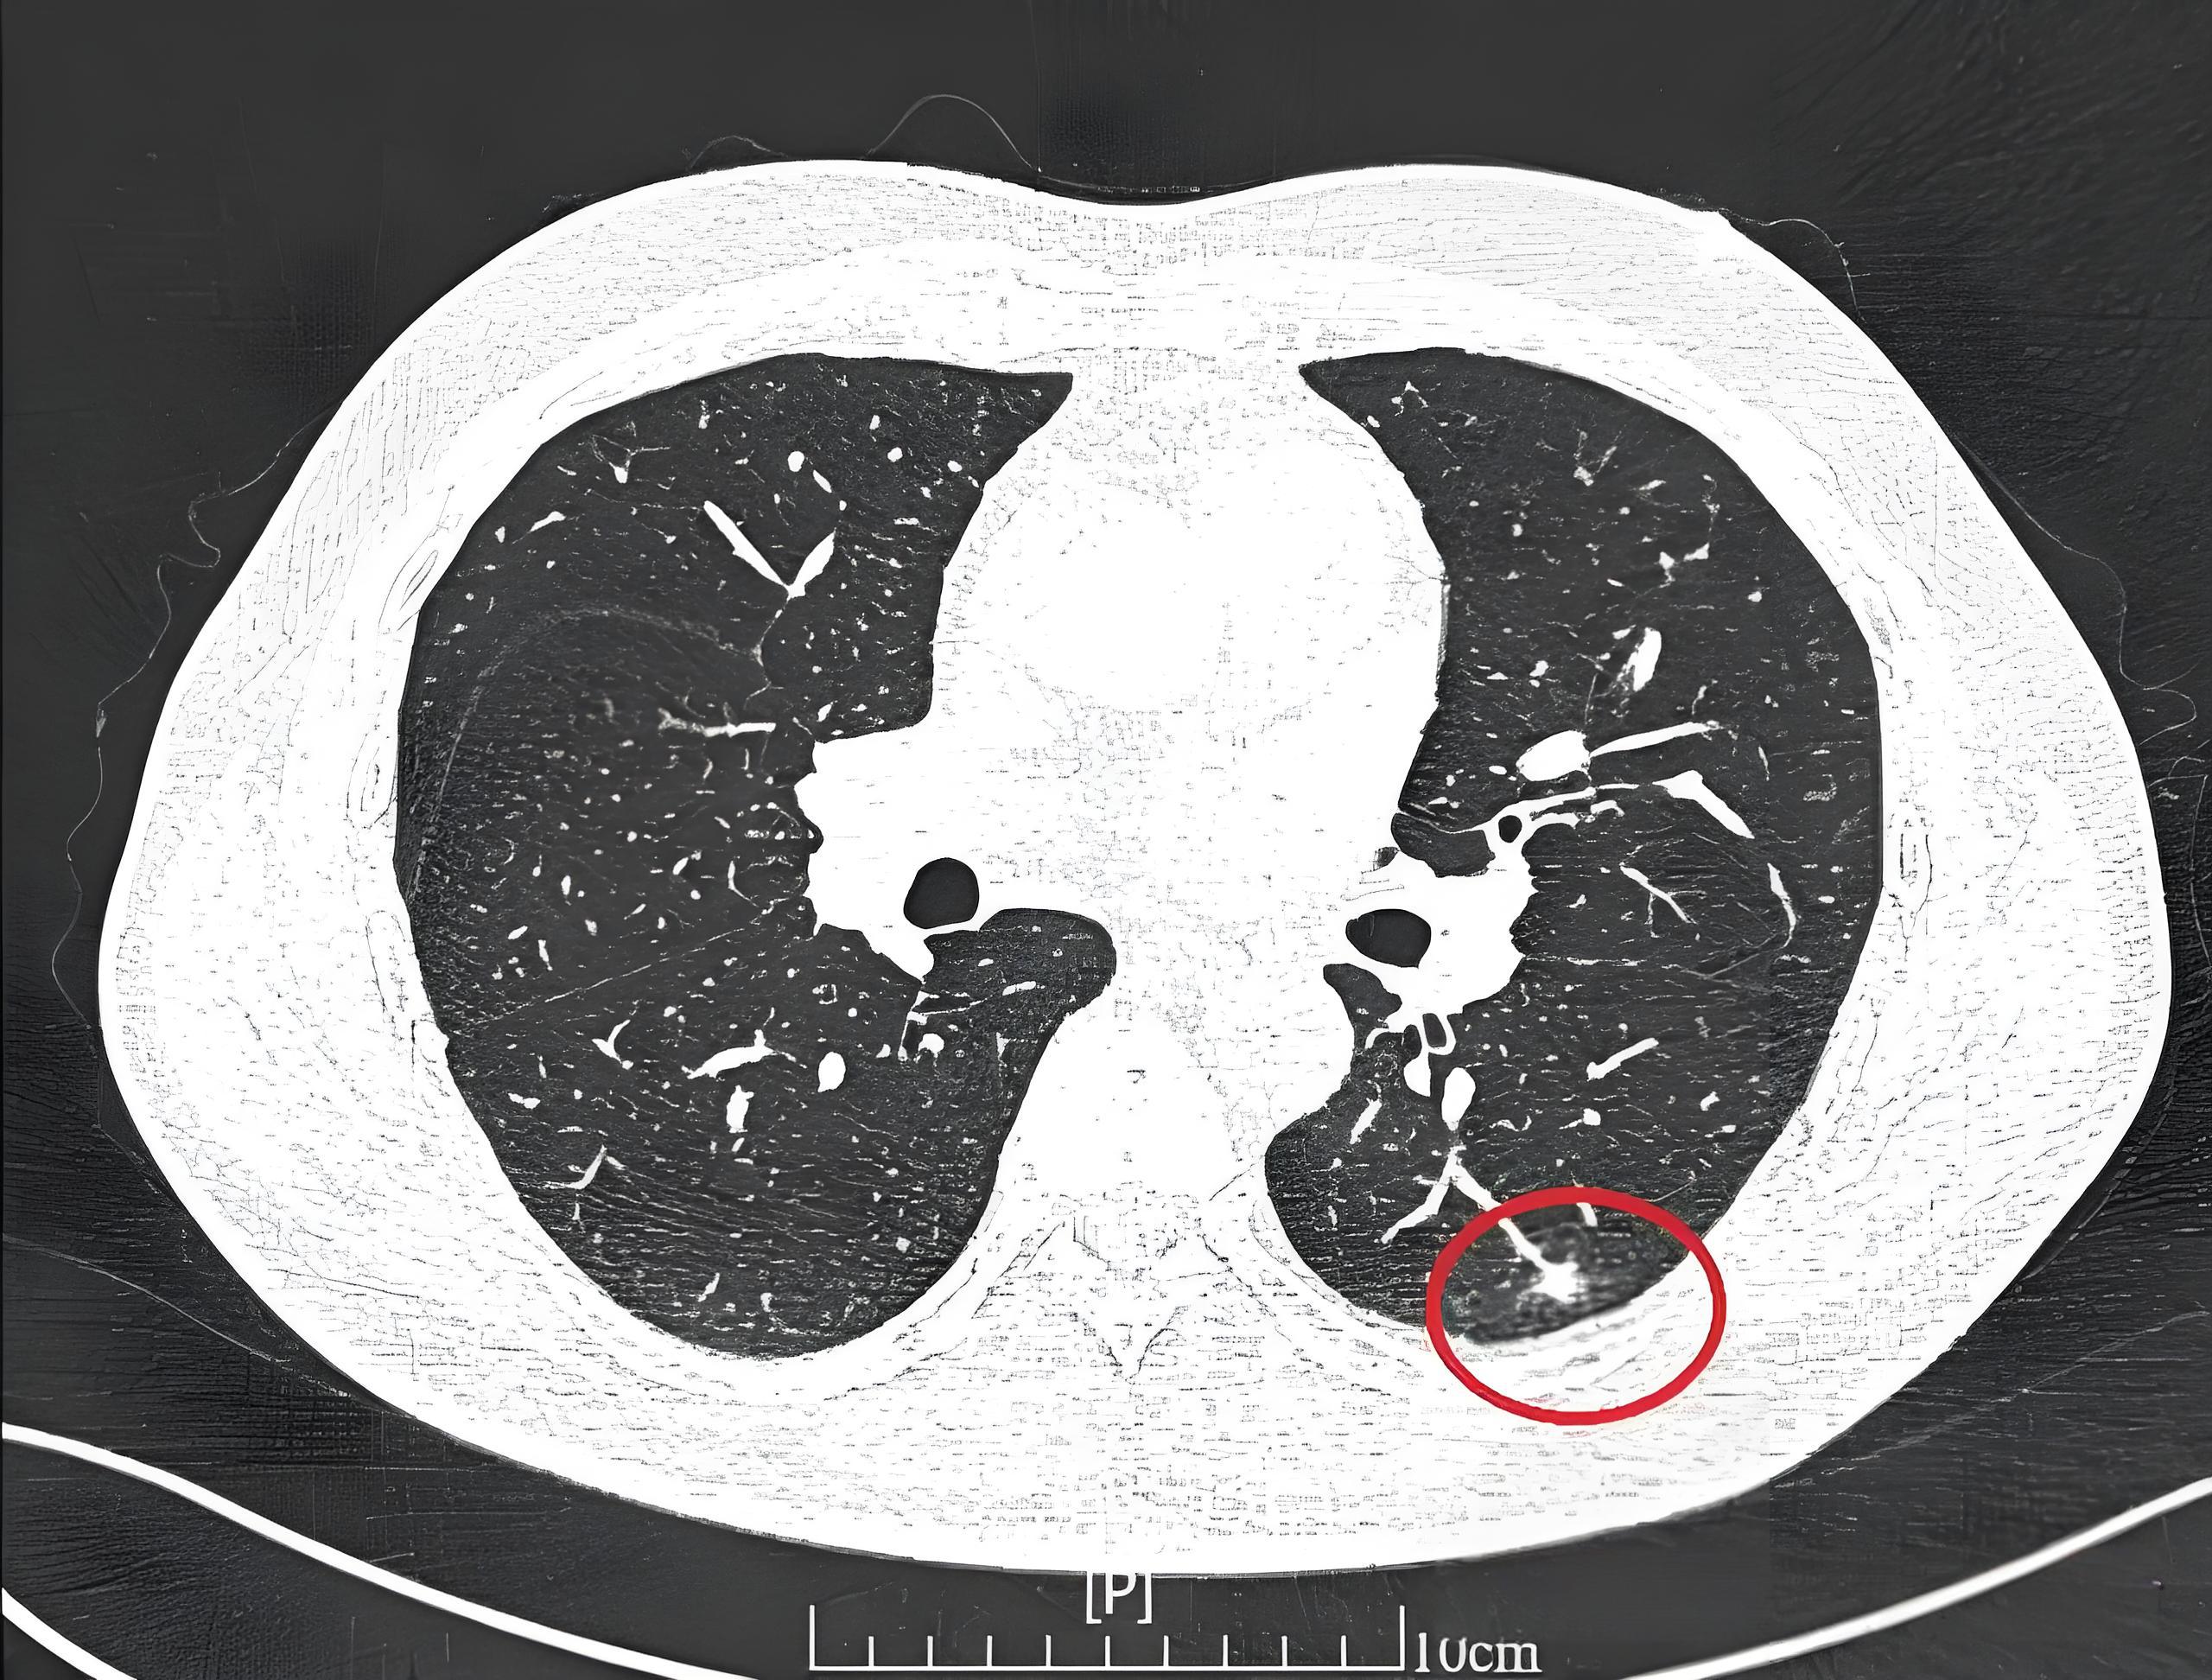

肺结节影什么意思

肺部结节影是指在肺部影像学检查中发现的小的局限性的圆形或椭圆形阴影以下是关于肺部结节影的详细解释定义与性质肺部结节影通常是指肺部出现的小于3厘米的局限性阴影,形状多为圆形或椭圆形它可能是由多种原因引起的,包括但不限于...